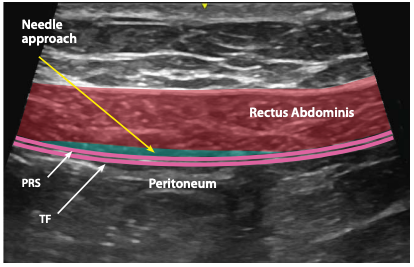

Rectus Sheath block

A

avoid inferior and superior epigastric arteries. Posterior sheath

In plane lateral to medial

20 mL each side 2 at level of umbilicus, 2 at midpoint between umbilicus and xiphoid

Arcuate line- posterior rectus sheath terminates- . 1/3 below umbi.